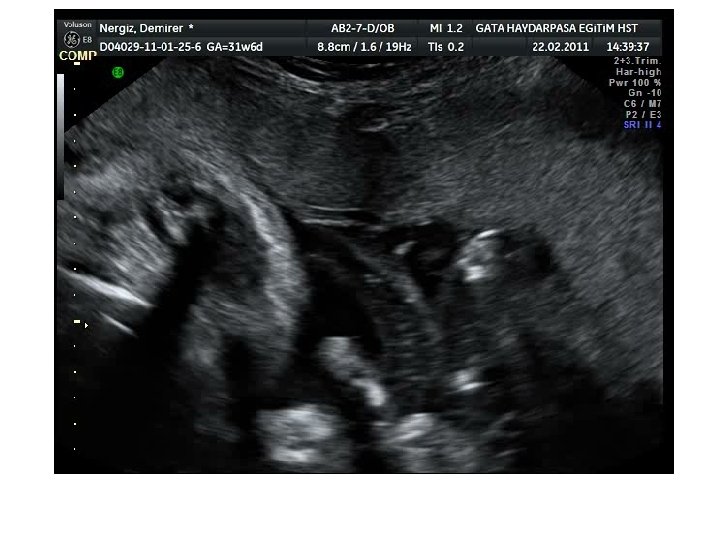

TANI YÖNTEMLERİ 5. Ultrasound: Alloimmünize gebeliklerin yönetimindeki en önemli gelişme ultrasonun kullanılmasıdır. – • • Gebelik haftasının doğru bir şekilde belirlenmesi: (MCA pik sistolik normal değerler gebelik haftasına göre değişir) Hidrops fetalis: En azından iki fetal kompartımanda ekstrasellüler sıvı varlığı olarak tanımlanır. – Asit, sıklıkla, yaklaşan hidropsun ilk belirtisidir. – Kötüleşen anemiyle birlikte scalp ödemi ve plevral efüzyon – Hydrops varsa, gebelik haftasına göre olması gereken ortalama hemoglobin değerinden 7 -10 g/d. L’lık fetal hemoglobin defisiti beklenebilir. – – Hidrops end-stage fetal anemiyi gösterir. Bu olgularda IUT’a rağmen sürvi belirgin ölçüde azalmıştır. Ayrıca, erken 2. trimesterde şiddetli anemik fetusta hidrops olmayabilir.

TANI YÖNTEMLERİ 5. Ultrasound: – Plasenta kalınlığı – Umblikal ven çapı – Karaciğer boyutu – Dalak boyutu – Polihidramniyos gibi sonografik bulguların fetal anemi prediksiyonunda yeterli güvenilirliği yok.